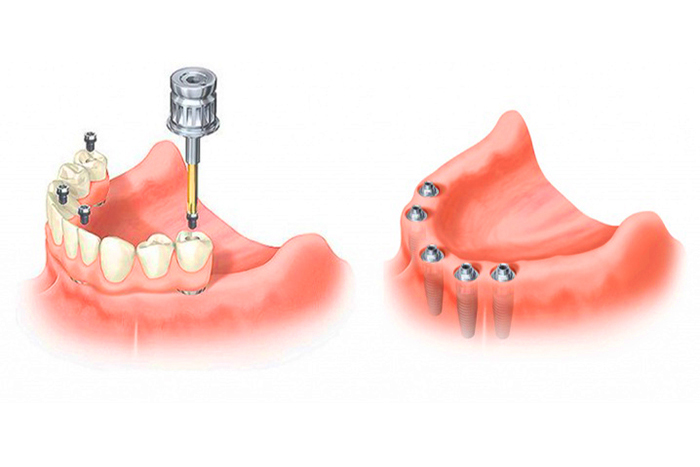

Пошаговое руководство по установке съёмного протеза на импланты